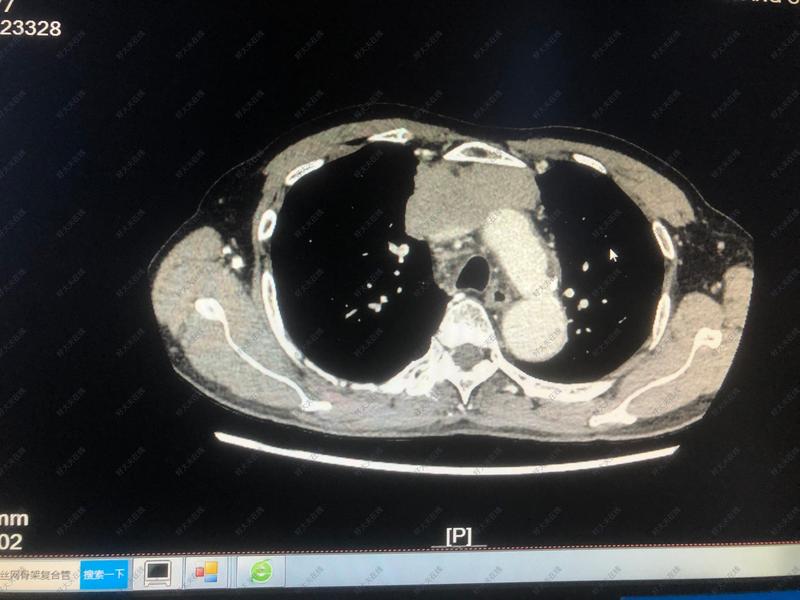

治療前 患者縱隔腫瘤侵犯上腔靜脈及左右無名靜脈、手術時把縱隔腫瘤完整切除,同時行上腔靜脈人工血管置管術。 治療中 手術中見腫瘤來源于胸腺,侵犯右肺上葉、上腔靜脈、右側隔神經(jīng)及左右無名靜脈。 治療后 治療后7天 手術后患者恢復順利,擬手術后3到4周返院行放化療等輔助治療